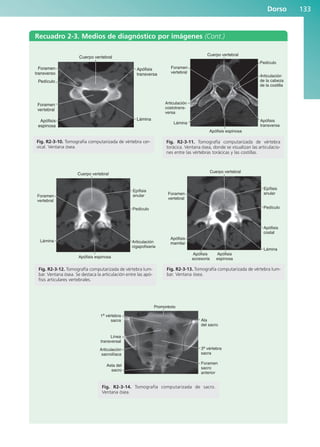

Recuadros de medios

de diagnóstico por

imágenes

En estos recuadros se agrupan

ejemplos de imágenes normales

de la región en estudio y se

fundamenta la aplicación de las

diversas técnicas para estudiar

las diferentes estructuras.